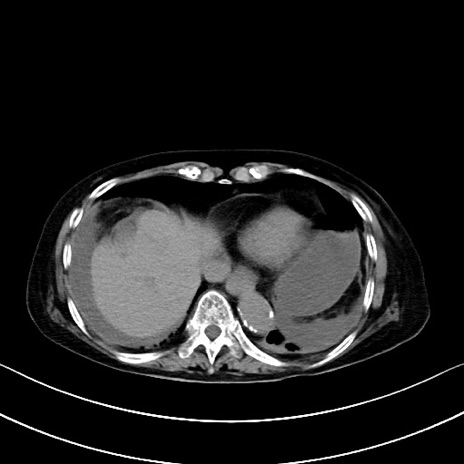

横断像

他院CT